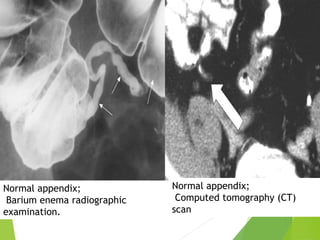

Normal appendix;

Barium enema radiographic

examination.

Computed tomography (CT)

scan